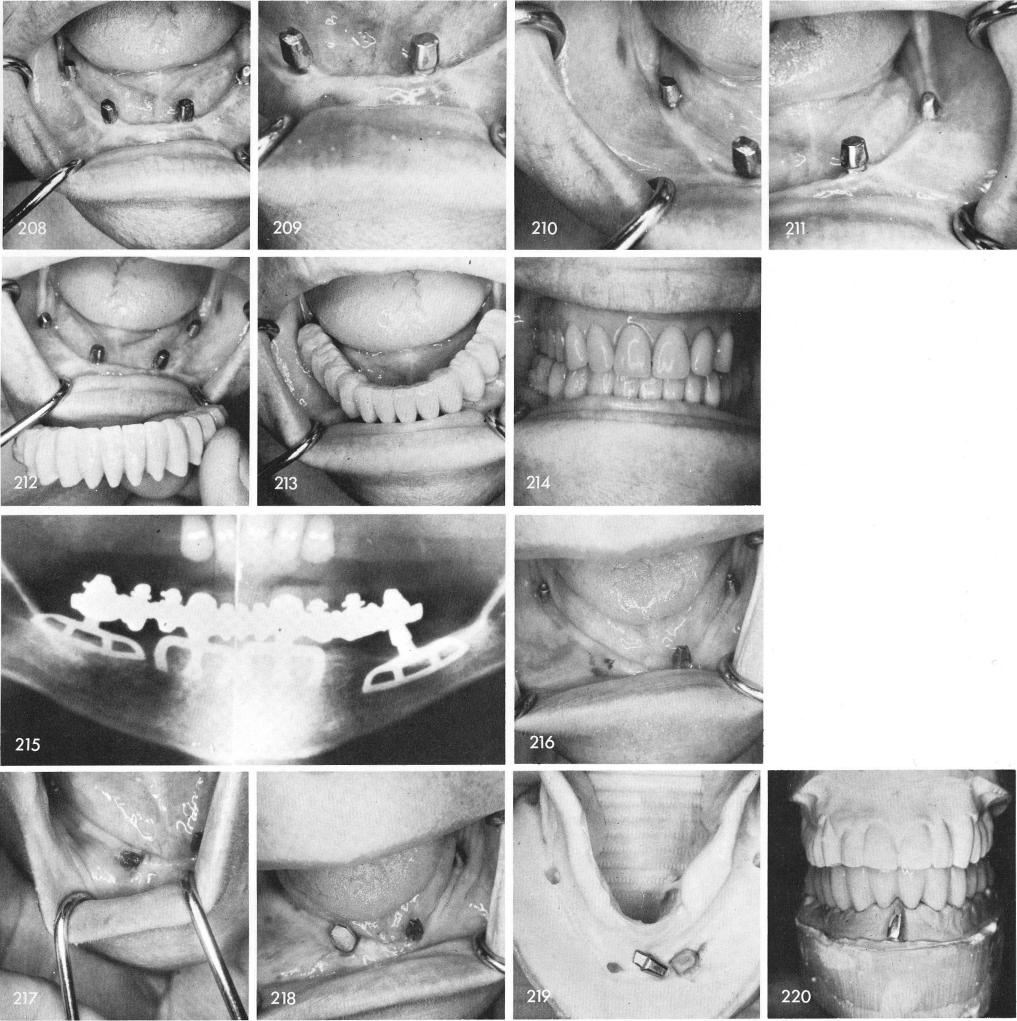

Four magnificently functioning blades are seen in figs. 208, 209, 210, 211. An acrylic over gold fixed prosthesis was cemented over the blade posts, figs. 212, 213, 214. This case was done at the Institute for Graduate Dentists in 1968 when the woman was in her middle seventies and still remains functioning with very little bone loss as seen on this nine year post-operative x-ray, fig. 215.

This case represents a very unusual and rare occurrence. Four bladevents functioned successfully for several years when one day she appeared in my office with the right cuspid neck of the blade severed completely from its body, fig. 216. The existing prosthesis had to be removed,

1 Mandibular blade implant posts after nine years of insertion